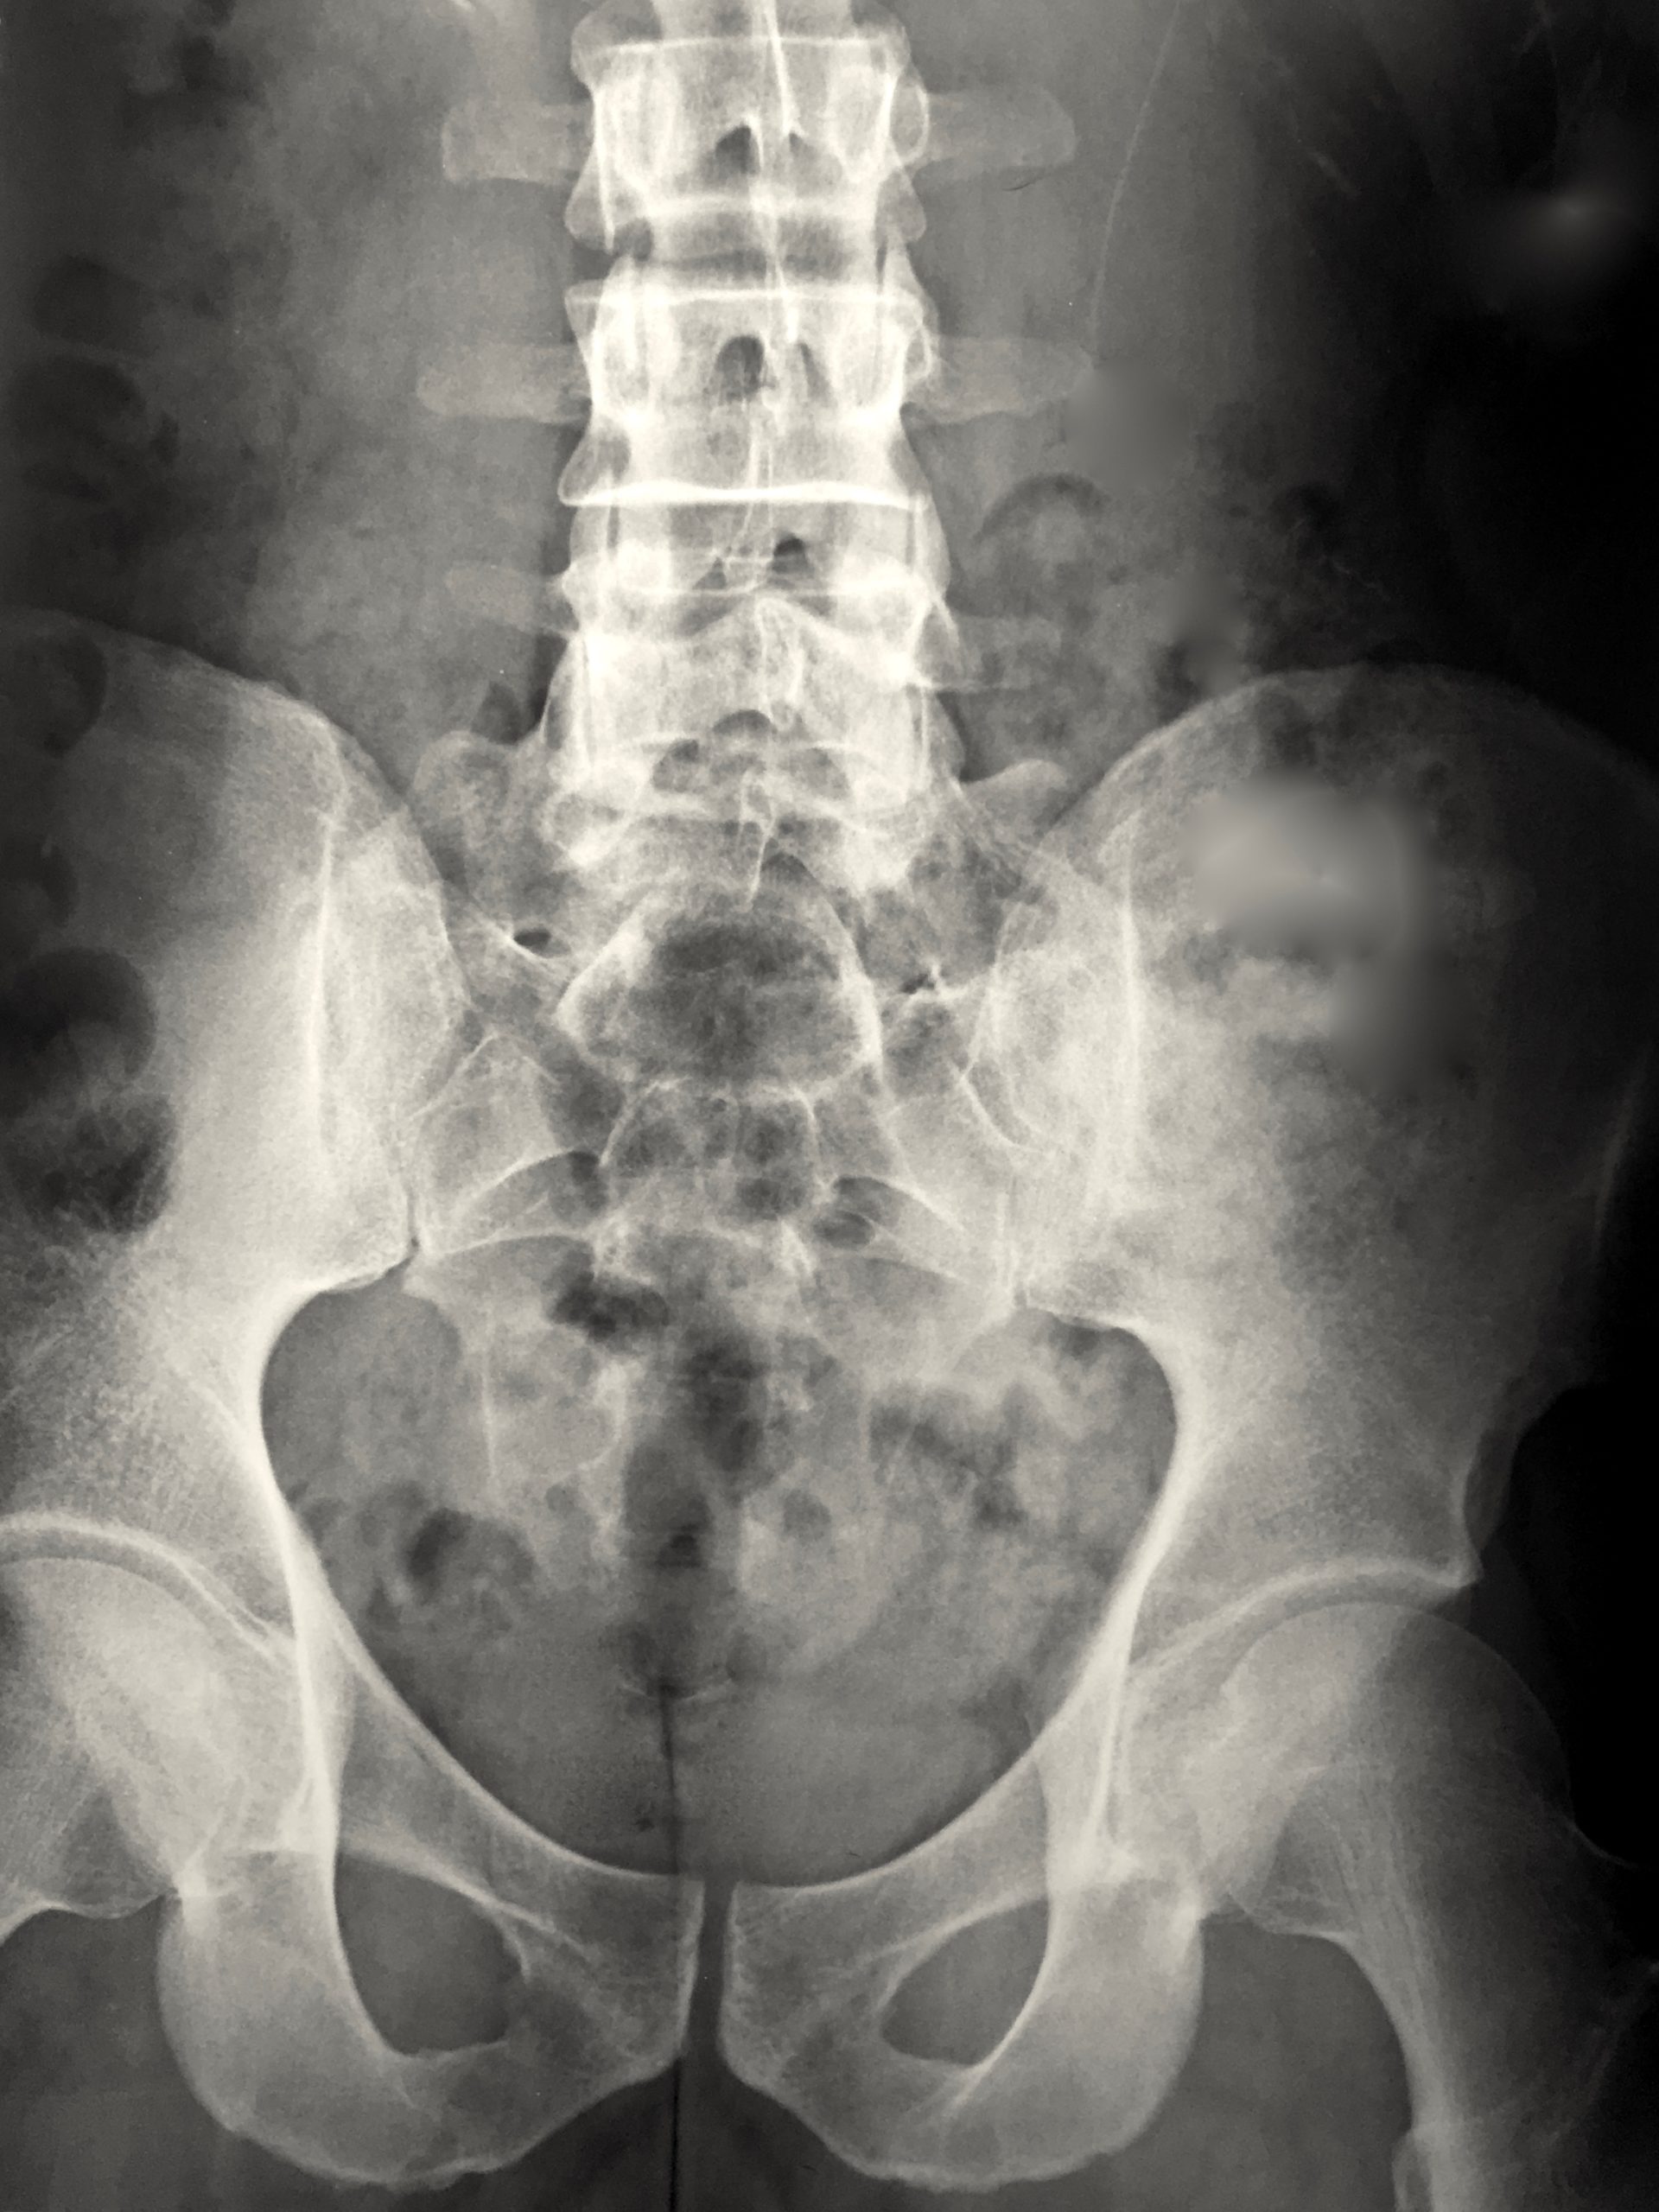

Scoliosis or a lateral curvature is not unusual, especially in women. When minimal, it often goes undiagnosed and unnoticed. However some people have a very pronounced and visible lateral spiral curve that disrupts structure and movement. This scoliotic spiralling pattern is NOT just about the spine – it is reflected throughout the ribs, the entire soft tissue container of the lungs and heart, and all surrounding musculature and fascias. The shoulders and pelvis are also affected in how they interface with the scoliotic torso. Whilst it may be impossible to unwind a complex scoliosis, it is possible to optimise structure and movement around it and through it, freducing pain and increasing mobility in the process.

Spinal conditions I work with include:

• Scoliosis with and without Harrington Rods